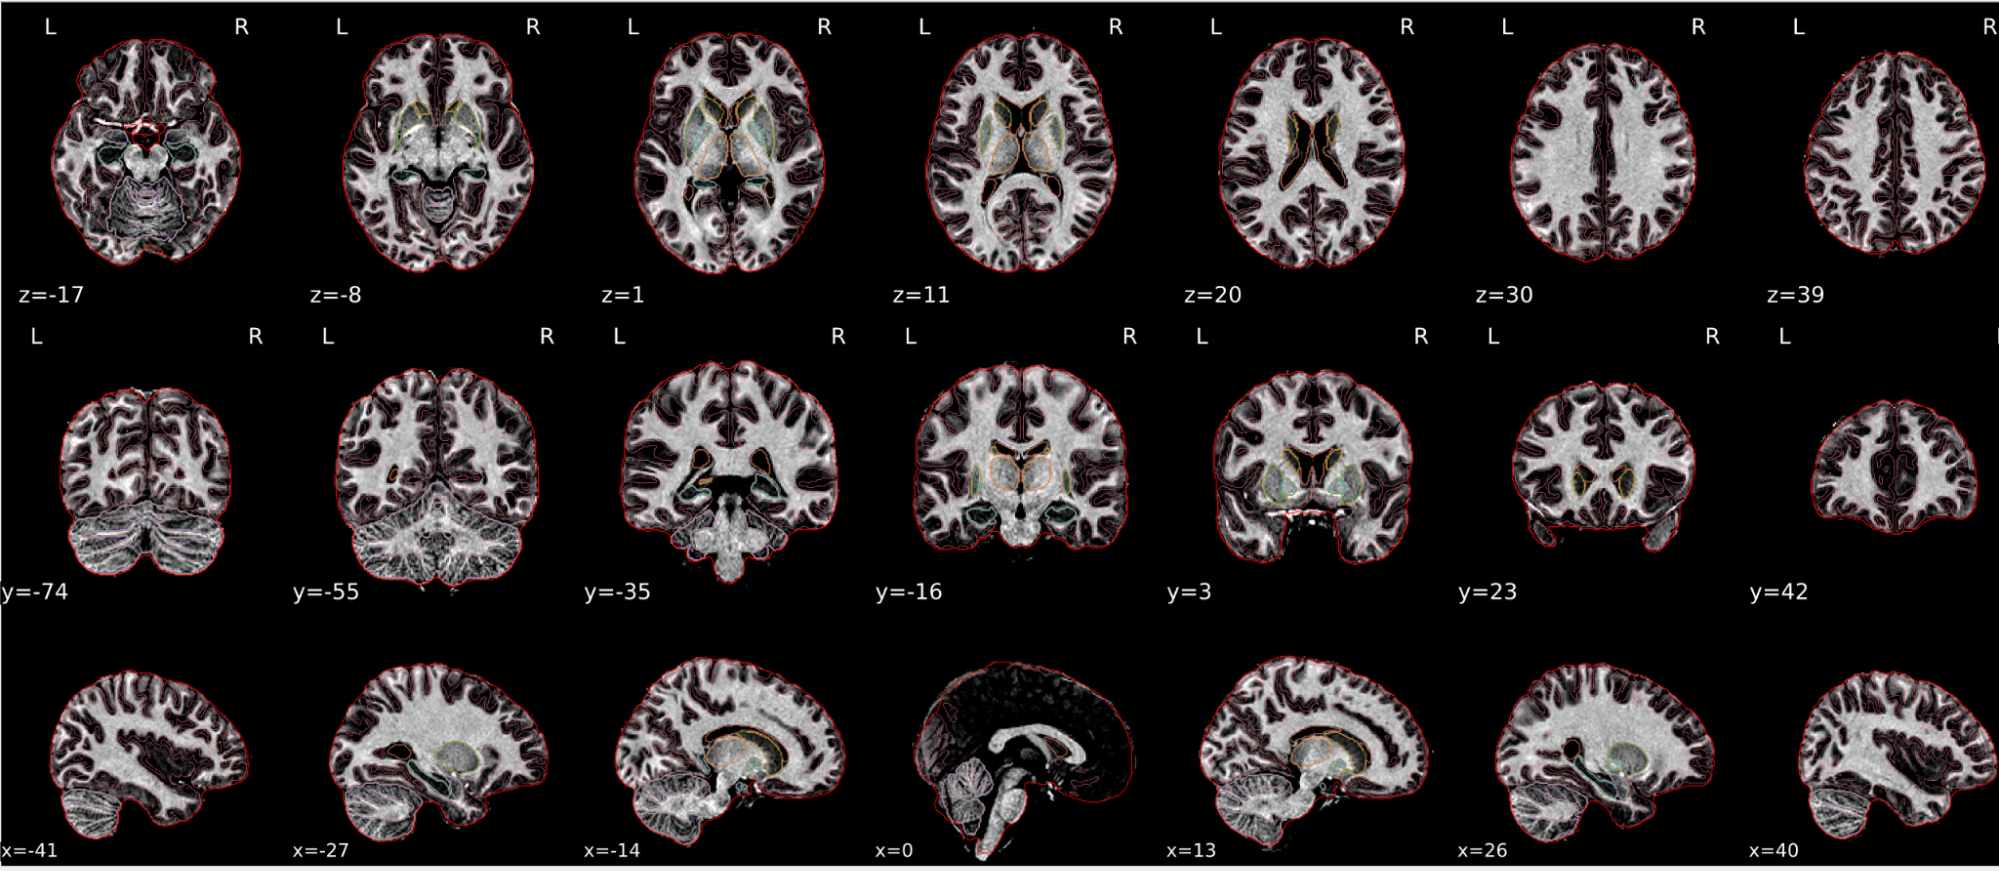

T1w skull stripping

Skull stripping is the process separating the brain (cortex and cerebellum) from the skull. The red line follows the outline of the brain and it separates it from the skull.

Example of a good subject

- There are no skull stripping errors, such as portions of the brain missing, or too much of the skull retained

- The red line follows the outline of the brain

Example of a bad subject

- There are skull stripping errors, such as portions of the brain missing, or too much of the skull retained

- NOTE: check all the images (slices) in the report. If only one image (slice) looks problematic, it is possible that the subject is okay and it is just a visual issue in that particular screenshot

Summary

| Good | Bad |

|---|---|

| The brain is fully inside the red line | Structures like the cranium or the eyes are inside the red line |

| No important brain structures are outside of the red line red line follows the natural outline of the brain | Important brain structures are missing inside of the red line |

-> if only one slice is problematic, it could be an issue related to the visual depiction of the data instead of an issue related to the test subject